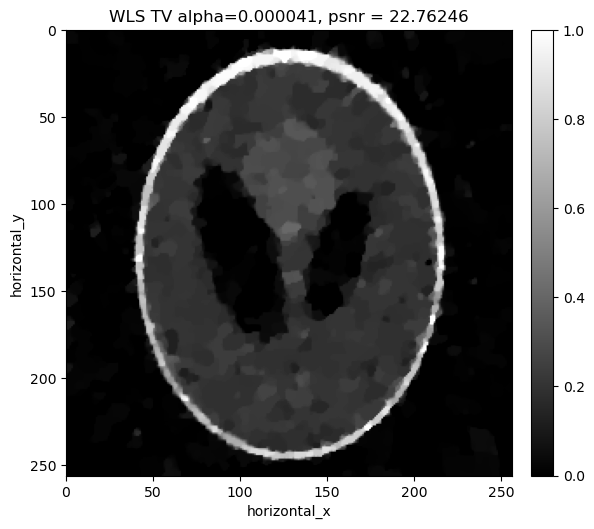

# get and visusualise the results

show2D([phantom, recon_fbp, recon_ls_tv_fista ], ["phantom, I0 = %7.0f" % (background_counts), "FBP, psnr= %5.3f" % (psnr_fbp),\

"LS TV FISTA alpha=%7.6f, psnr= %5.3f" % (alpha_ls_tv_fista,psnr_ls_tv_fista)], \

cmap=cmap, fix_range =(0,1), num_cols=3, size=(15,10), origin='upper-left')

../../_images/demos_LS_WLS_KL_TotalVariation_37_0.png

[30]:

#Visualise the results

show2D([phantom, recon_fbp, recon_wls_tv_fista ], ["phantom, I0 = %7.0f" % (background_counts), "FBP, psnr= %5.3f" % (psnr_fbp),\

"WLS TV FISTA alpha=%7.6f, psnr= %5.3f" % (alpha_wls_tv_fista,psnr_wls_tv_fista)], \

../../_images/demos_LS_WLS_KL_TotalVariation_43_0.png

[35]:

#Visualise the reconstructions

show2D([phantom, recon_fbp, recon_kl_tv_fista ], ["phantom, I0 = %7.0f" % (background_counts), "FBP, psnr= %5.3f" % (psnr_fbp),\

"KL TV FISTA alpha=%7.6f, psnr= %5.3f" % (alpha_kl_tv_fista,psnr_kl_tv_fista)], \

../../_images/demos_LS_WLS_KL_TotalVariation_52_0.png

[37]:

show2D([phantom, recon_fbp, recon_ls_tv_fista,recon_wls_tv_fista, recon_kl_tv_fista ], ["phantom, I0 = %7.0f" % (background_counts), "FBP, psnr= %5.3f" % (psnr_fbp),\ "LS TV FISTA alpha=%7.6f, psnr= %5.3f" % (alpha_ls_tv_fista,psnr_ls_tv_fista),\ "WLS TV FISTA alpha=%7.6f, psnr= %5.3f" % (alpha_wls_tv_fista,psnr_wls_tv_fista), \ "KL TV FISTA alpha=%7.6f, psnr= %5.3f" % (alpha_kl_tv_fista,psnr_kl_tv_fista)], \ cmap=cmap, fix_range =(0,1), num_cols=3, origin='upper-left')

../../_images/demos_LS_WLS_KL_TotalVariation_55_0.png